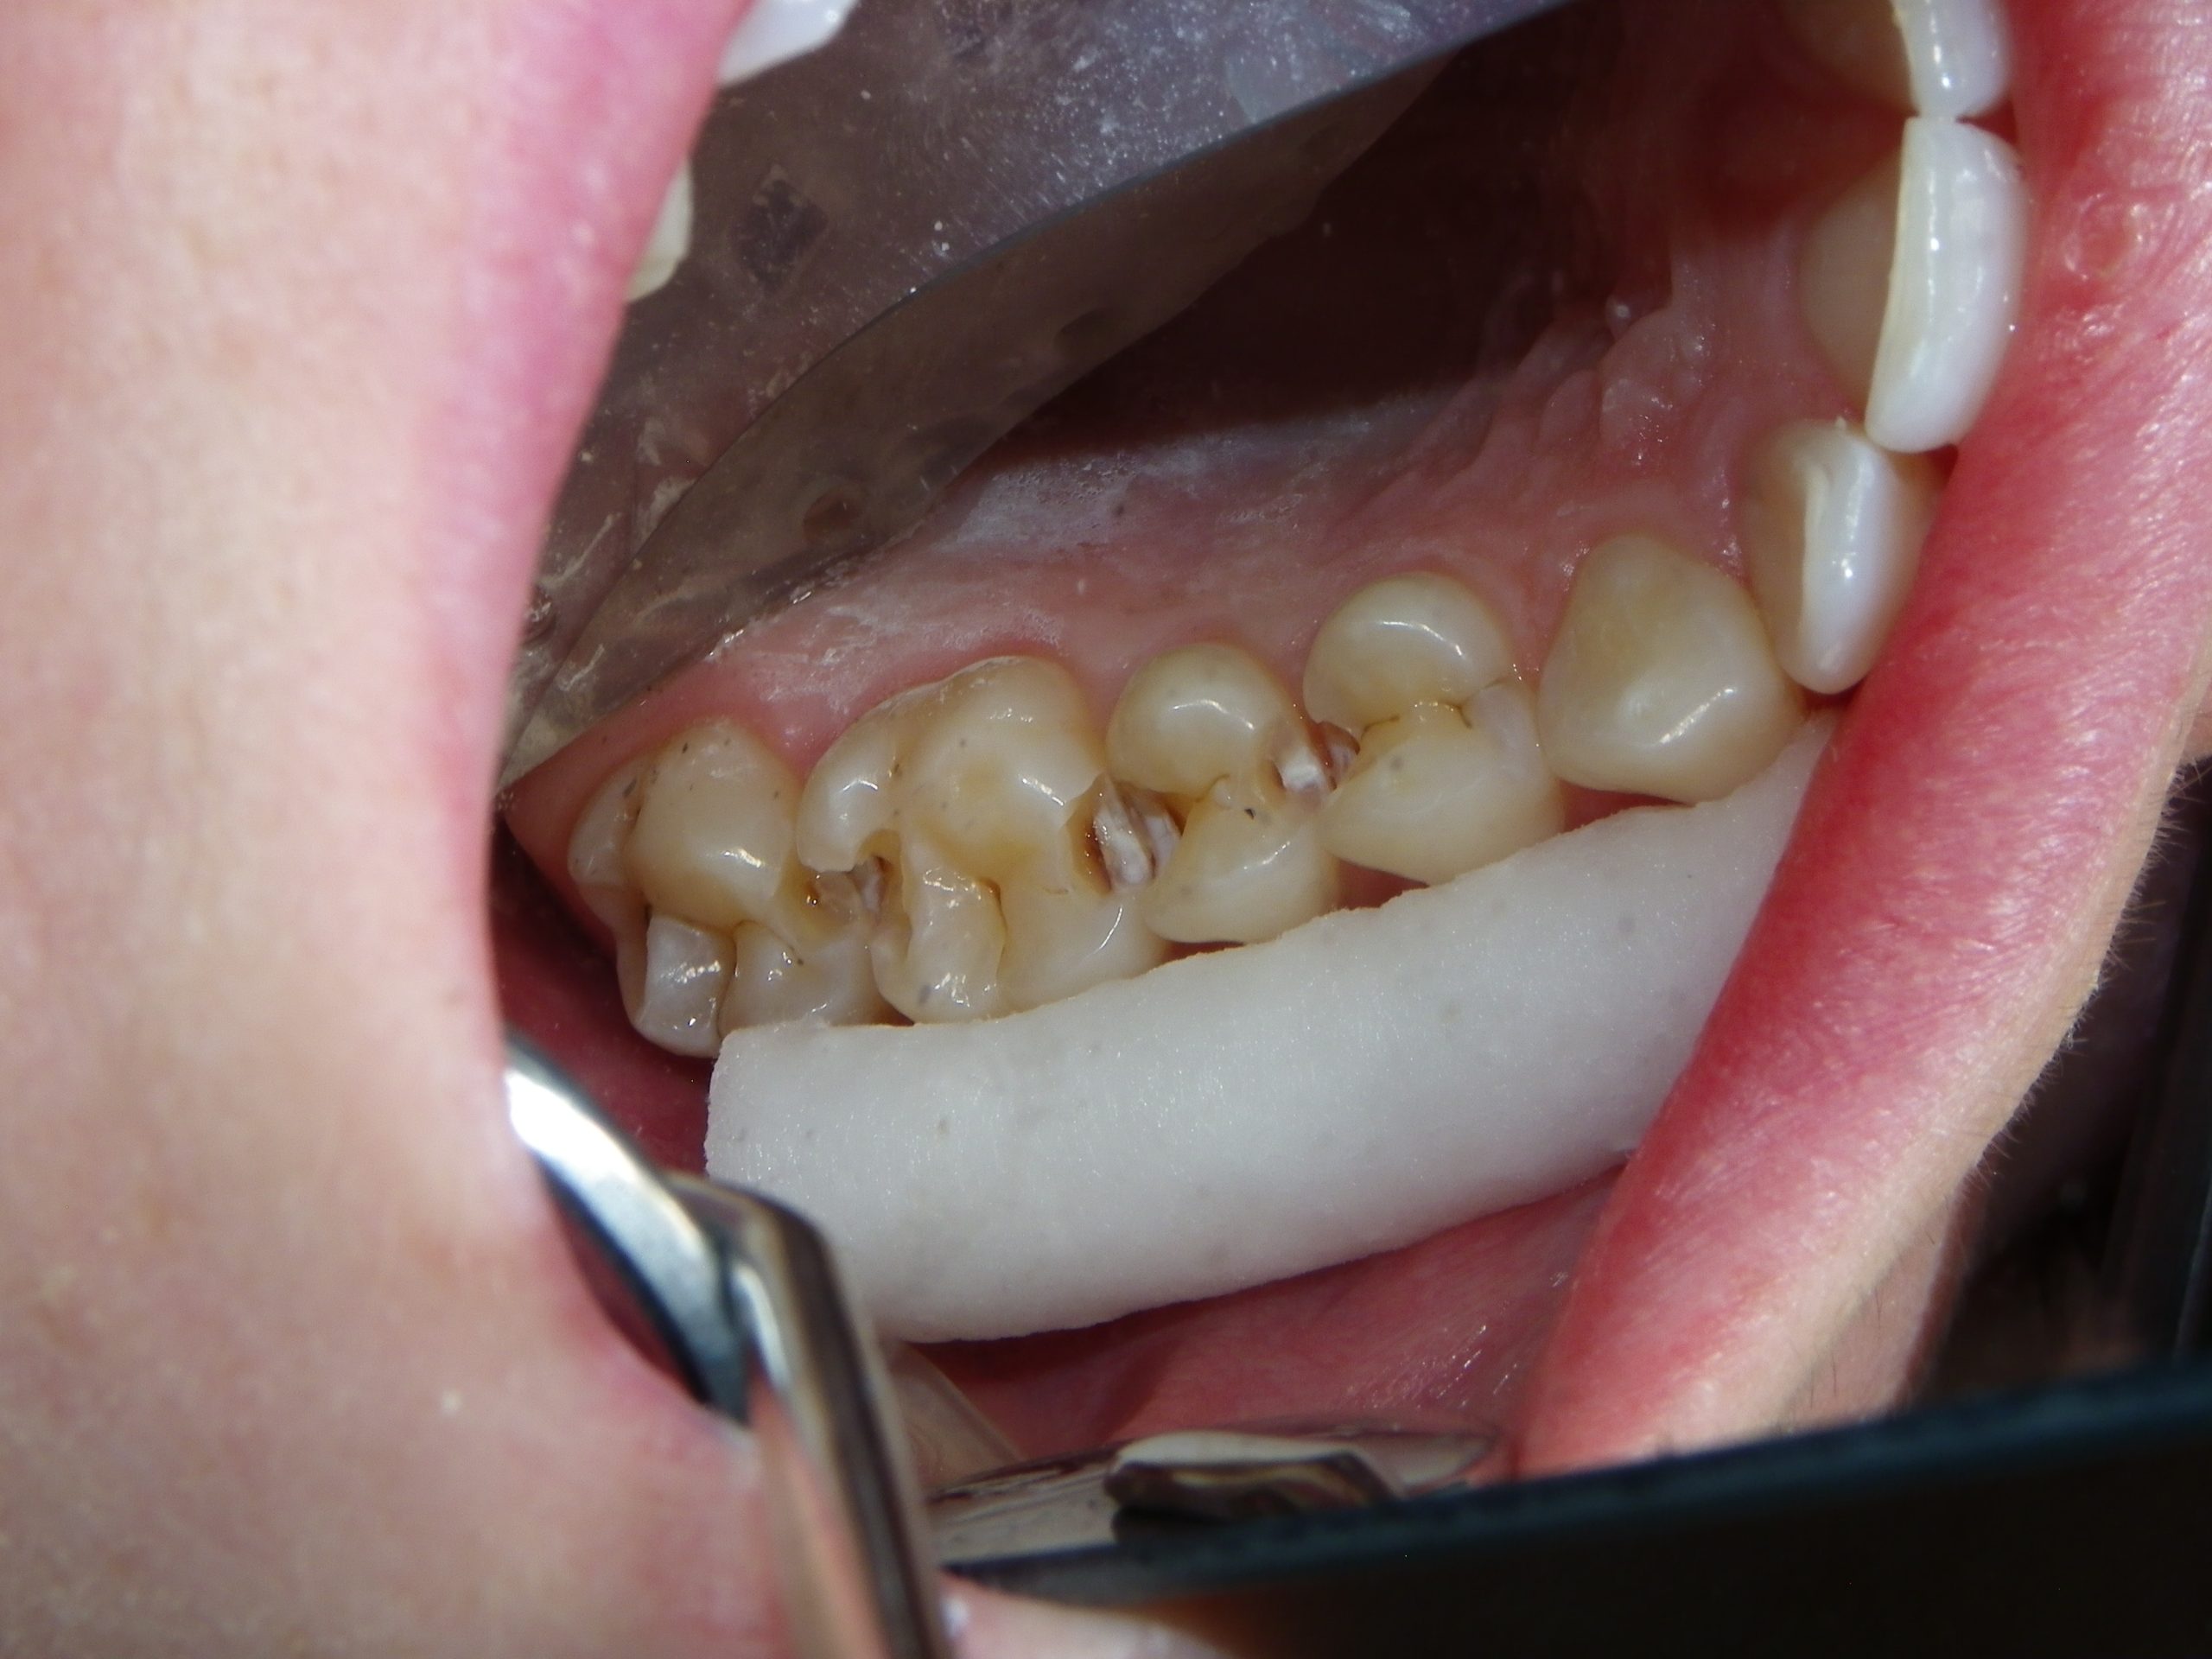

After educating the patient on the decay risks of this behaviour, oral hygiene instruction and a recommendation for a daily fluoride rinse, she can now take action to prevent any new cavities from developing for the rest of her life. There were many areas of decay between other teeth that we elected not to fill due to their small size, and hopefully they remain arrested / remineralized! (Aluminum oxide Air abrasion via PrepStart, 32% Phosphoric acid etch with Benzalkonium Chloride and AllBond Universal adhesive from Curion, Esthet-X Flowable A2 liner from Dentsply, Simplishade Medium resin core from Kerr).